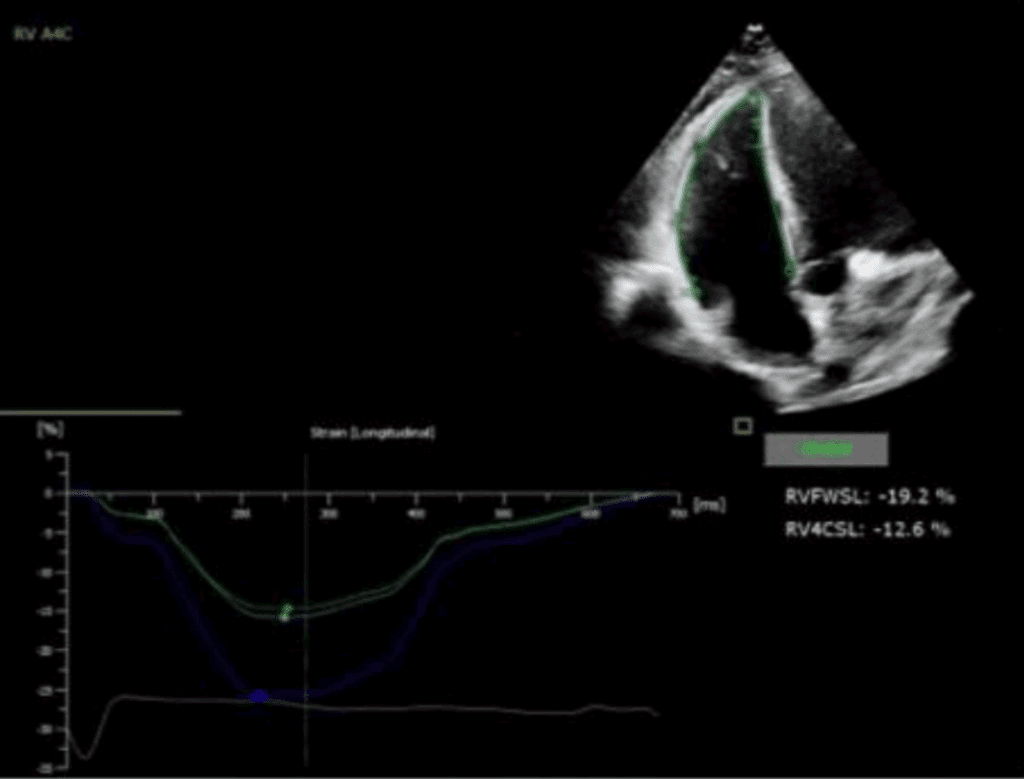

Odkształcenie mięśnia sercowego (strain) jest metodą diagnostyczną oraz coraz lepiej udokumentowanym parametrem prognostycznym, który uzupełnia standardowe przezklatkowe badanie echokardiograficzne (ang. transthoracic echocardiography – TTE).